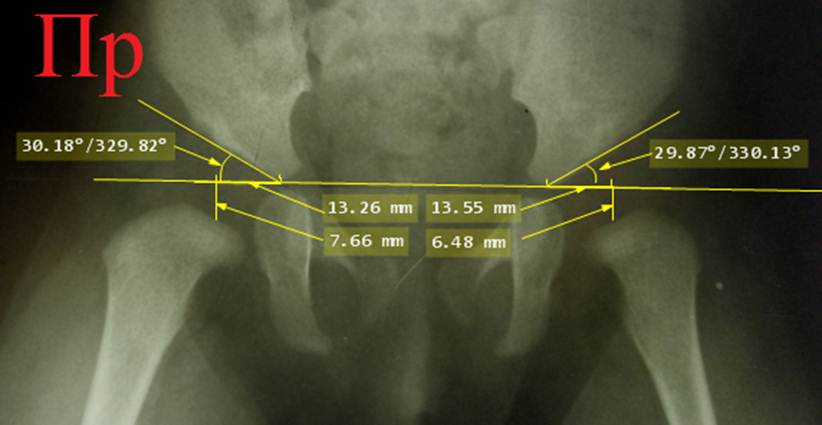

вытяжения. Это же относится и к случаям успешного вправления, в которых

Снимок

ребенка 7 месяцев, расчерчивание по Хильгенрейнеру. Двухсторонняя дисплазия

тазобедренных суставов с децентрацией: обратите внимание на вертикальные и

горизонтальные позиции, ацетабулярные углы

и положение ядер окостенения головок относительно линий Омбредана - Перкинса.

Постановка диагноза запоздалая. Назначено консервативное лечение с помощью

отводящей шины БелНИИТО (она применяется

редко и не имеет преимуществ перед другими).